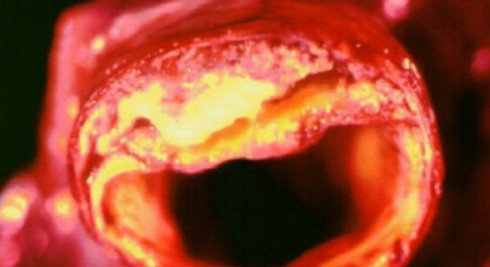

고혈압은 수치가 높은 것만으로도 위험하지만 합병증이 동반되면 더욱 심각해집니다. 심한 경우 생명까지 위협할 수 있어 철저한 관리가 필요합니다. 뇌출혈, 뇌경색, 치매 등 뇌 질환을 유발할 수 있으며, 눈에는 망막증이나 심하면 실명으로 이어질 수 있습니다. 또한 심장에도 부담을 주어 협심증, 신부전, 심근경색 등이 발생할 수 있습니다.